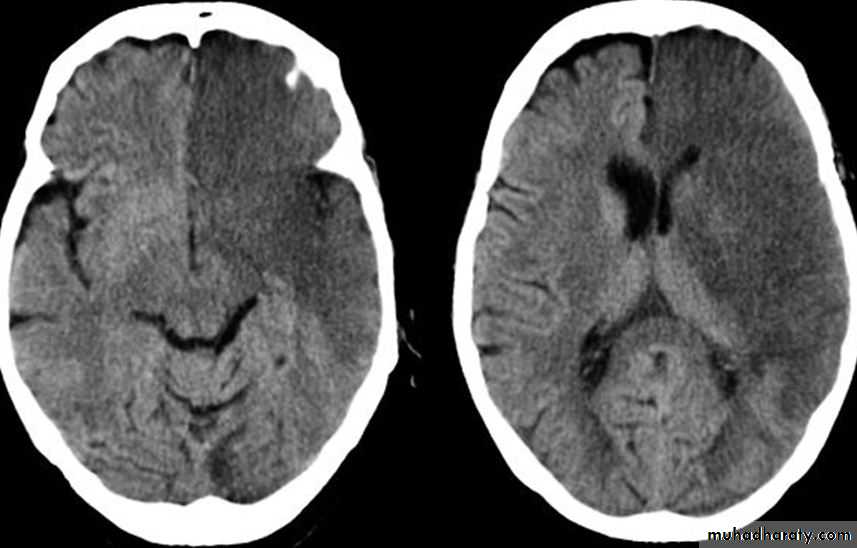

• How to identify patients with tissue at risk for guidance in selecting the appropriate therapy

• Exclude hemorrhage• Differentiate between irreversibly affected brain tissue and reversibly impaired tissue (dead tissue versus tissue at risk)

• Identify stenosis or occlusion of major extra- and intracranial arteries